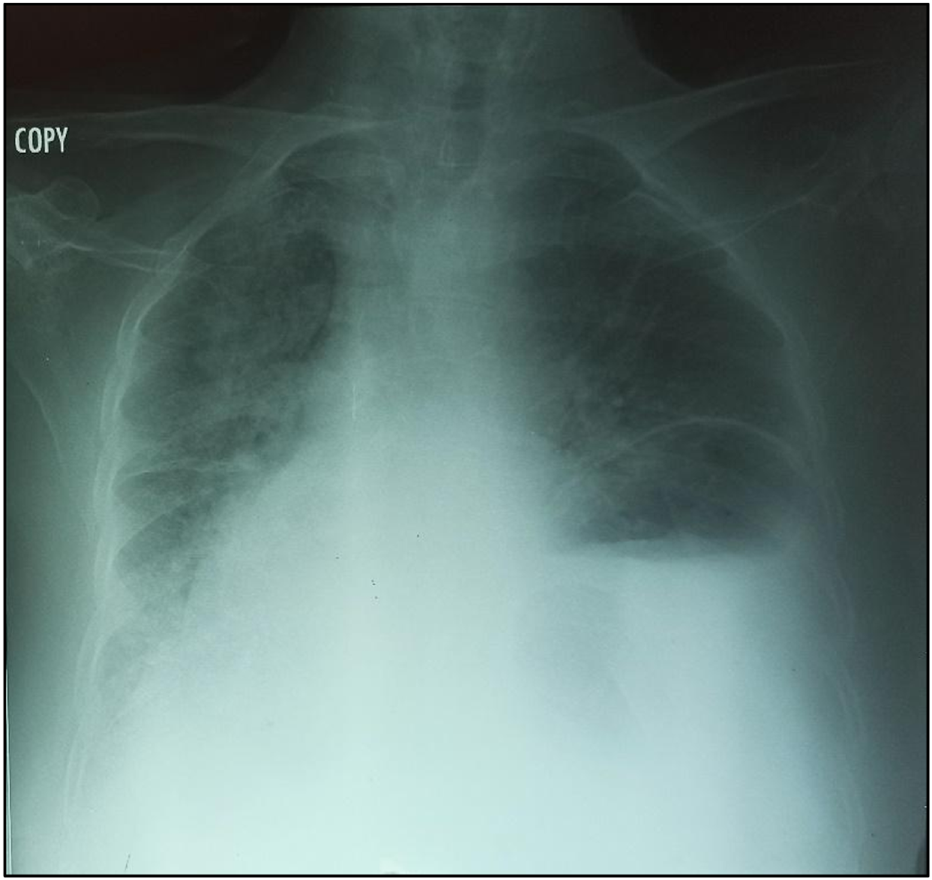

In October 2021, an 88-year-old Black woman presented with a history of hypertension and epigastric pain for 30 years. She had no history of thoracic or abdominal trauma. She was admitted with respiratory distress, constipation, and abdominal pain lasting 24 h. On admission, her Glasgow coma score was 15/15, her oxygen saturation was 89% in ambient air, she had a fever of 38.5 °C, her blood pressure was 110/90 mmHg, her heart rate was 111 beats per minute, her respiratory rate was 32 cycles per minute, and she had a distended, soft abdomen without tenderness (Figure 3A). Paraclinical examinations revealed leukocytosis of 12,000 cells per IU, with neutrophil predominance associated with lymphopenia at 700 cells/IU. The C-Reactive Protein level was 192 mg/L. At this time, it was a unique diagnostic we suspect due to the epidmiology context. Initial investigations included a rapid COVID-19 test, a PCR test for COVID-19, and a chest X-ray. The former two were negative, but the latter showed a gastric pocket in the left chest (Figure 1). We suspected a diaphragmatic hernia. The following day, the patient underwent thoracoabdominal computed tomography, which revealed a left posterolateral diaphragmatic hernia with signs of intestinal necrosis, suggesting strangulation; the PCR test for confirmation of a SARS-CoV-2 infection was negative. Other anomalies seen during the CT scans included the spleen and stomach in the left chest, condensation in the right lung, and right pleural effusion (Figure 2). An electrocardiogram showed sinus tachycardia, and a heart ultrasound showed dextrocardia with a normal left ventricular ejection fraction. Initial resuscitation consisted of hydration with normal saline, insertion of a nasogastric tube, and a Foley catheter. The patient then underwent a mid-laparotomy performed by two senior consultants in general surgery, which revealed a 7-cm left Bochdalek hernia orifice containing the stomach and the spleen which had been accidentally lacerated, and 1 m of necrotic ileum (Figures 3B,C). The herniated contents were returned to the abdominal cavity, the hernia orifice was repaired with interrupted non-absorbable stitches, and a splenectomy and resection of the necrotic ileum with loop stoma formation were performed. The chest and abdomen were drained. The patient was admitted to the intensive care unit (ICU) on mechanical ventilation. She received a course of ceftriaxone (4 g/day) and metronidazole (500 mg/8 h) in addition to other supportive care. She was intubated until the third post-operative day, and on that day, she experienced progressive multiorgan dysfunction, including haematological, renal, and central nervous system dysfunction. She died on the fourth day after the surgery.

FIGURE 1

Chest radiography showing enlargement of the mediastinum and the gastric pocket in the left chest.